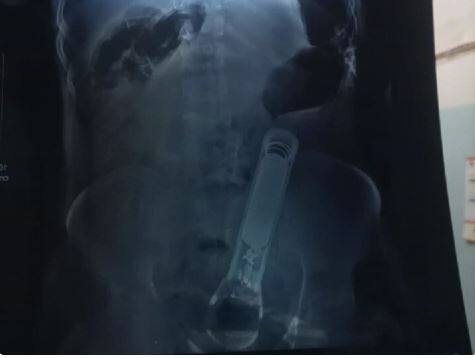

ਗੋਪਾਲਗੰਜ: ਬਿਹਾਰ ਦੇ ਗੋਪਾਲਗੰਜ 'ਚ ਇੱਕ ਹੈਰਾਨੀਜਨਕ ਮਾਮਲਾ ਸਾਹਮਣੇ ਆਇਆ ਹੈ। ਜਨਮ ਦਿਨ ਪਾਰਟੀ 'ਚ ਡਾਂਸ ਕਰਨ ਤੋਂ ਇਨਕਾਰ ਕਰਨ 'ਤੇ ਦਬੰਗਾਂ ਨੇ ਬੇਰਹਿਮੀ ਦੀਆਂ ਸਾਰੀਆਂ ਹੱਦਾਂ ਪਾਰ ਕਰ ਦਿੱਤੀਆਂ। ਉਸ ਦੇ ਪ੍ਰਾਈਵੇਟ ਪਾਰਟ 'ਚ ਟਾਰਚ ਪਾ ਦਿੱਤੀ। ਇਸ ਤੋਂ ਪਹਿਲਾਂ ਉਕਤ ਵਿਅਕਤੀਆਂ ਨੇ ਉਸ ਦੀ ਬੇਰਹਿਮੀ ਨਾਲ ਕੁੱਟਮਾਰ ਵੀ ਕੀਤੀ। ਪੁਲਿਸ ਨੂੰ ਸ਼ਿਕਾਇਤ ਕਰਨ 'ਤੇ ਜਾਨੋਂ ਮਾਰਨ ਦੀਆਂ ਧਮਕੀਆਂ ਵੀ ਦੇ ਰਹੇ ਹਨ।

ਮਾਮਲਾ ਮਾਂਝਾਗੜ੍ਹ ਥਾਣਾ ਖੇਤਰ ਦਾ ਹੈ। ਪੁਲਿਸ ਨੇ ਇਸ ਮਾਮਲੇ 'ਚ ਐਫਆਈਆਰ ਦਰਜ ਕਰਕੇ ਇੱਕ ਮੁਲਜ਼ਮ ਨੂੰ ਗ੍ਰਿਫ਼ਤਾਰ ਕਰ ਲਿਆ ਹੈ। ਦੂਜੇ ਪਾਸੇ ਪੀੜਤ ਦੇ ਪਰਿਵਾਰਕ ਮੈਂਬਰਾਂ ਨੇ ਇਲਾਜ ਲਈ ਸਥਾਨਕ ਸਰਕਾਰੀ ਹਸਪਤਾਲ 'ਚ ਦਾਖਲ ਕਰਵਾਇਆ, ਜਿੱਥੋਂ ਡਾਕਟਰਾਂ ਨੇ ਗੋਰਖਪੁਰ ਰੈਫਰ ਕਰ ਦਿੱਤਾ। ਇਸ ਤੋਂ ਬਾਅਦ ਪਰਿਵਾਰ ਵਾਲੇ ਉਸ ਨੂੰ ਇੱਕ ਨਿੱਜੀ ਹਸਪਤਾਲ ਲੈ ਗਏ, ਜਿੱਥੇ ਆਪ੍ਰੇਸ਼ਨ ਕਰਕੇ ਢਿੱਡ 'ਚ ਫਸੀ ਟਾਰਚ ਨੂੰ ਬਾਹਰ ਕੱਢਿਆ ਗਿਆ।

ਦੱਸਿਆ ਜਾ ਰਿਹਾ ਹੈ ਕਿ 26 ਜੂਨ ਦੀ ਰਾਤ ਨੂੰ ਪਿੰਡ 'ਚ ਜਨਮ ਦਿਨ ਦੀ ਪਾਰਟੀ ਸੀ। ਪੀੜਤ ਨੌਜਵਾਨ ਨੂੰ ਬੁਲਾਉਣ ਲਈ ਚਾਰ ਵਿਅਕਤੀ ਘਰ ਆਏ ਸਨ, ਜਦੋਂ ਉਹ ਉੱਥੇ ਗਏ ਤਾਂ ਉਨ੍ਹਾਂ ਨੂੰ ਨੱਚਣ ਲਈ ਕਹਿਣ ਲੱਗੇ। ਜਦੋਂ ਨੌਜਵਾਨ ਨੇ ਇਨਕਾਰ ਕੀਤਾ ਤਾਂ ਉਸ ਦੀ ਕੁੱਟਮਾਰ ਕੀਤੀ ਗਈ। ਇਸ ਦੌਰਾਨ ਚਾਰਾਂ ਨੌਜਵਾਨਾਂ ਨੇ ਮਿਲ ਕੇ ਪ੍ਰਾਈਵੇਟ ਪਾਰਟ ਤੋਂ ਲੋਹੇ ਦੀ ਟਾਰਚ ਪਾ ਦਿੱਤੀ। ਜਦੋਂ ਪੀੜਤ ਨੇ ਘਰ ਆ ਕੇ ਸਾਰੀ ਘਟਨਾ ਆਪਣੀ ਪਤਨੀ ਤੇ ਪਰਿਵਾਰਕ ਮੈਂਬਰਾਂ ਨੂੰ ਦੱਸੀ ਤਾਂ ਉਸ ਨੂੰ ਤੁਰੰਤ ਇਲਾਜ ਲਈ ਹਸਪਤਾਲ ਲਿਜਾਇਆ ਗਿਆ, ਜਿੱਥੇ ਡਾਕਟਰਾਂ ਨੇ ਉਸ ਨੂੰ ਗੋਰਖਪੁਰ ਰੈਫਰ ਕਰ ਦਿੱਤਾ।